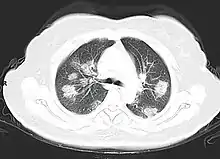

Imaging

Chest CT scans may be helpful to diagnose COVID‑19 in individuals with a high clinical suspicion of infection but are not recommended for routine screening.[165][177] Bilateral multilobar ground-glass opacities with a peripheral, asymmetric, and posterior distribution are common in early infection.[165][178] Subpleural dominance, crazy paving (lobular septal thickening with variable alveolar filling), and consolidation may appear as the disease progresses.[165][179] Characteristic imaging features on chest radiographs and computed tomography (CT) of people who are symptomatic include asymmetric peripheral ground-glass opacities without pleural effusions.[180]

Many groups have created COVID‑19 datasets that include imagery such as the Italian Radiological Society which has compiled an international online database of imaging findings for confirmed cases.[181] Due to overlap with other infections such as adenovirus, imaging without confirmation by rRT-PCR is of limited specificity in identifying COVID‑19.[180] A large study in China compared chest CT results to PCR and demonstrated that though imaging is less specific for the infection, it is faster and more sensitive.[164]